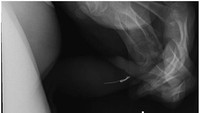

Ada benda lainnya yang dimasukkan ke dalam uretra pria yang diketahui memiliki riwayat masalah kejiwaan. Rontgen panggul tampak lateral mengidentifikasi kawat logam dari masker wajah rumah sakit di uretra penis distal, yang dikeluarkan secara spontan. (Foto: Adam Bezinque/ jurnal Frontiers In)